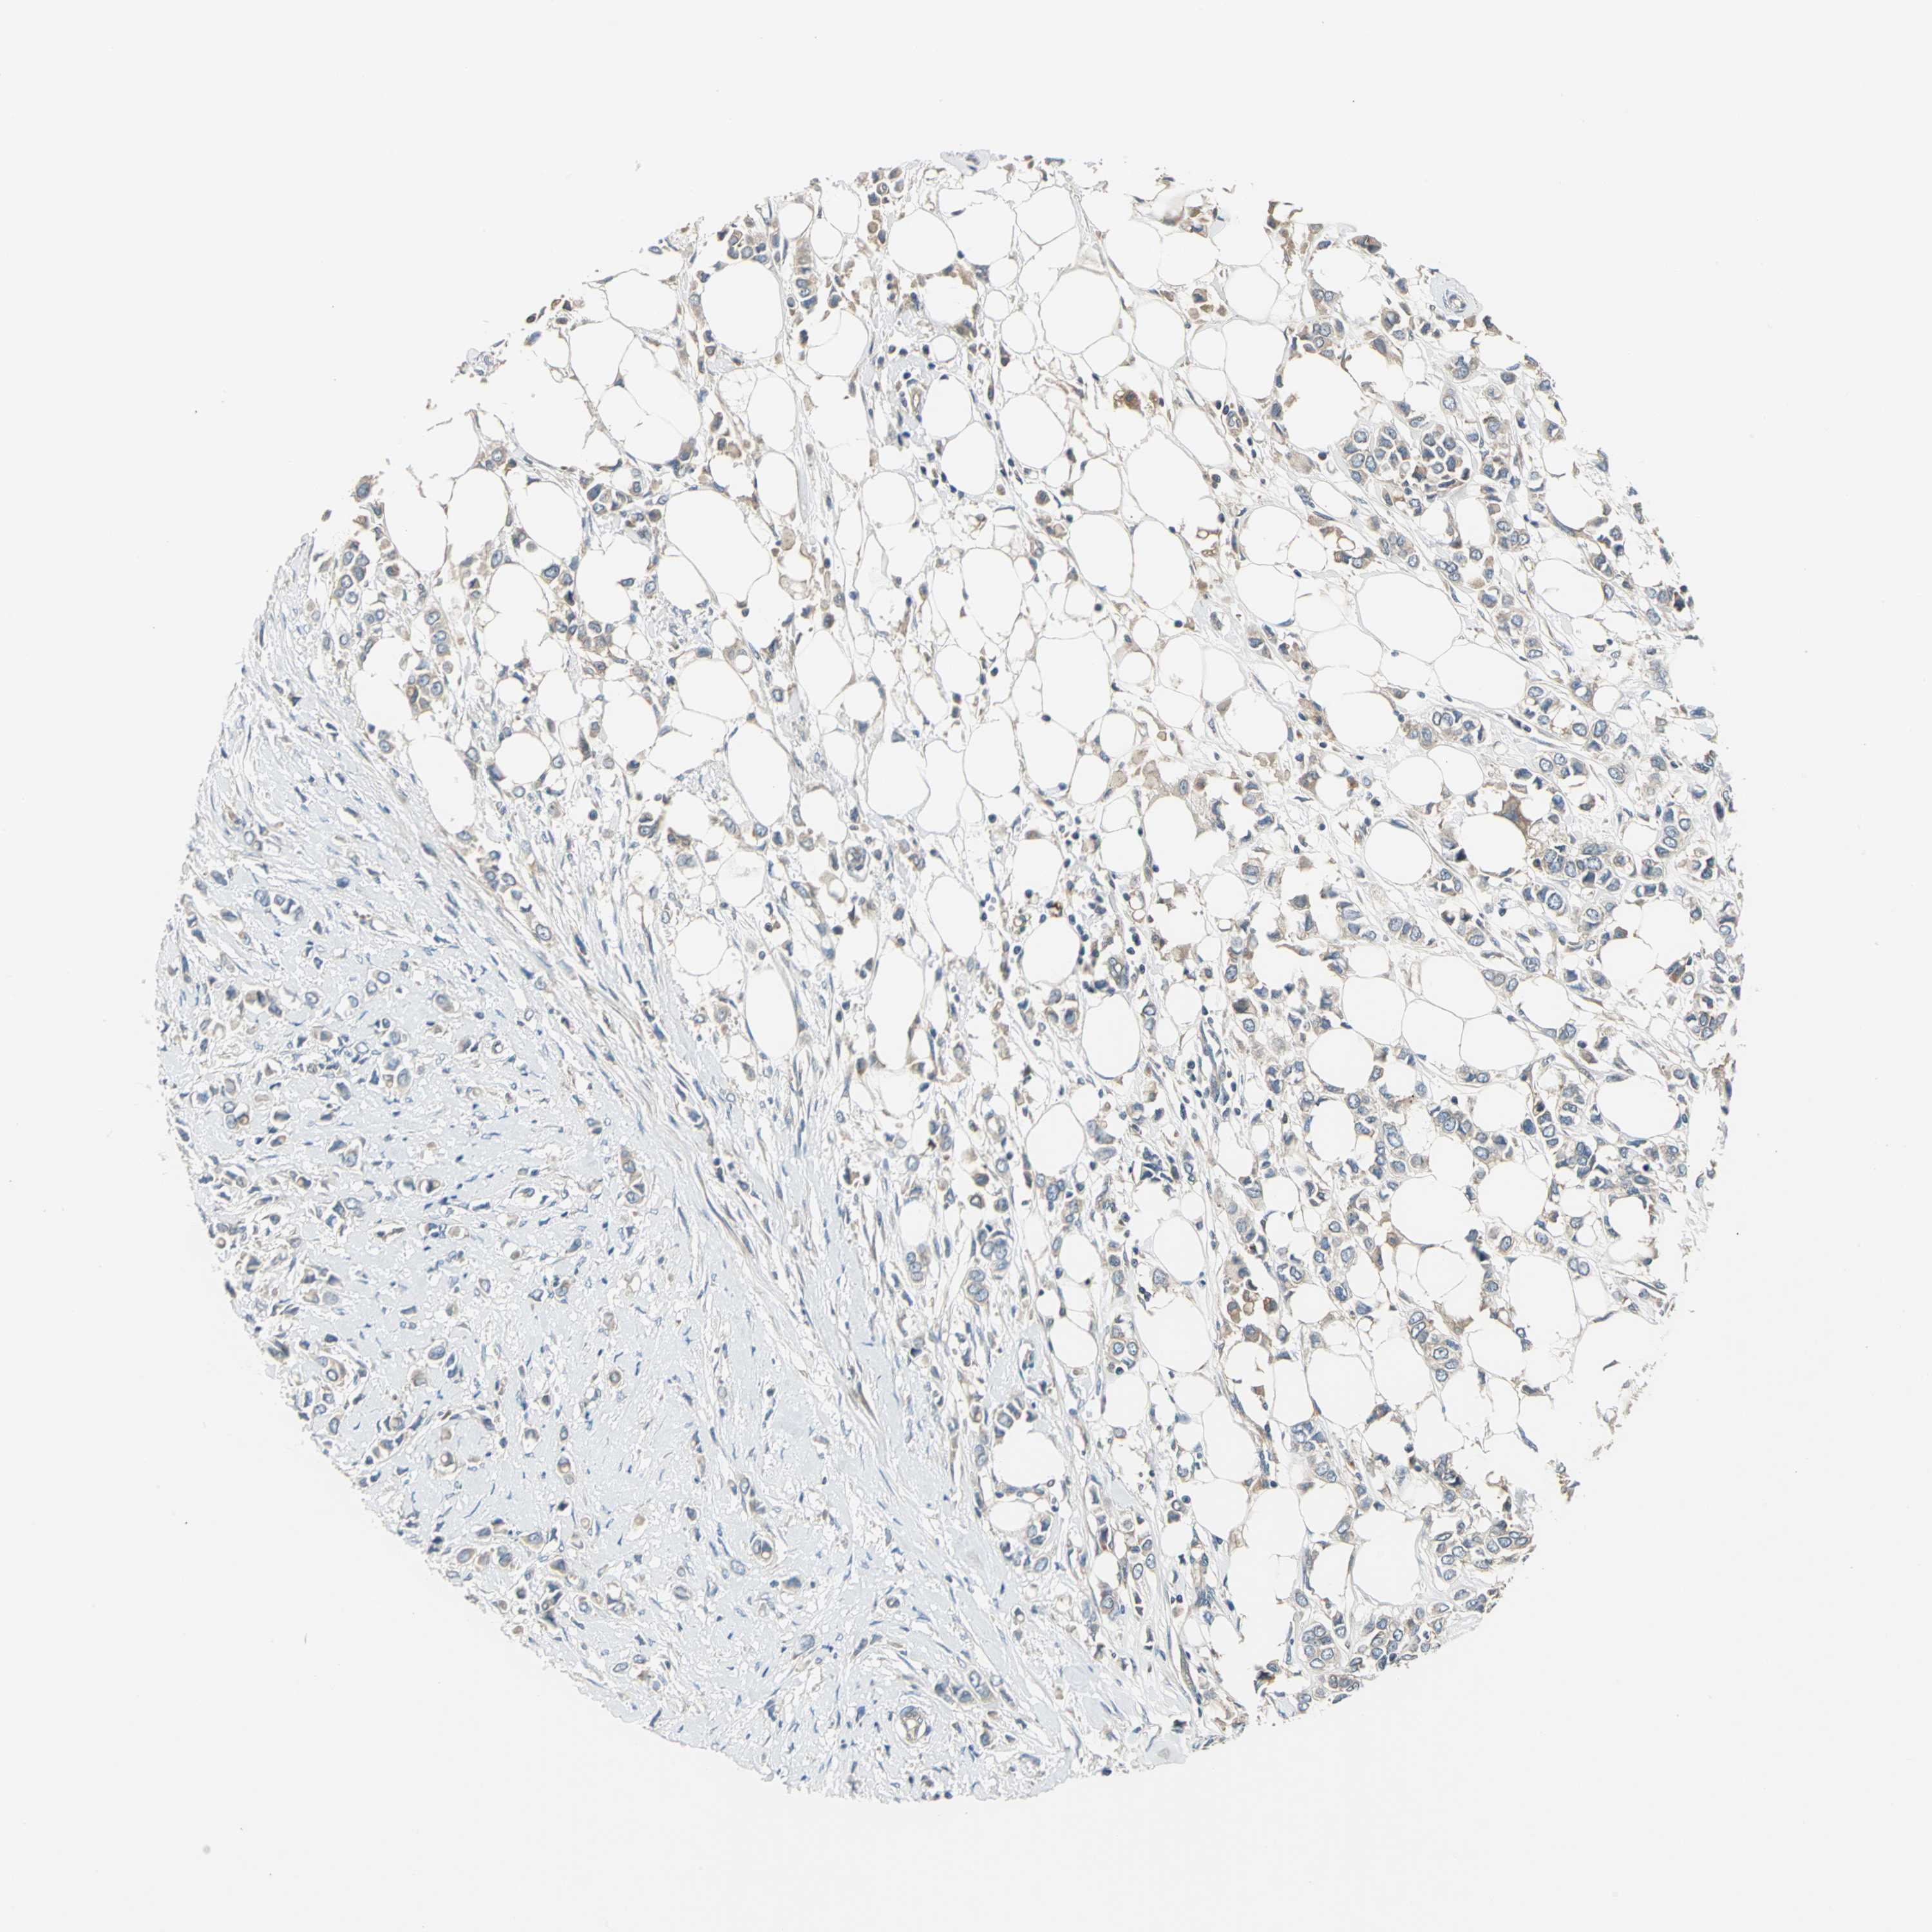

CANCER BREAST CANCER Show tissue menu

BRCA TCGA BRCA VALIDATION PROTEIN EXPRESSION